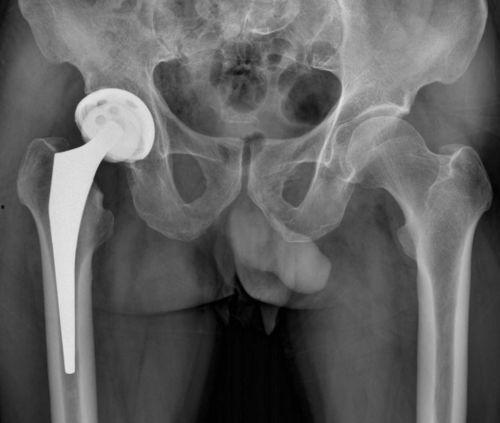

股骨头术后康复是一个漫长而艰辛的过程,它关系到你能否恢复到术前的生活状态。正确的康复训练不仅能够帮助你减轻疼痛,还能加速骨头的愈合,预防并发症。所以,选择合适的康复训练动作视频至关重要。